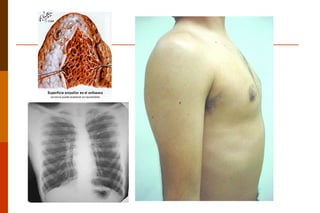

O enfisema pulmonar está presente quando muitos alvéolos estão destruídos e os restantes ficam com o seu funcionamento alterado, decorrente de agressão crônica ao parênquima pulmonar.  Macroscopicamente:  observa-se pulmões aumentados de volume, inelásticos e com bolhas especialmente nas margens e nos ápices. Diminuição da elasticidade. . DPOC -  enfisema pulmonar

Enfisema caraterizado por cavitação única próxima a superfície pleural com limites nítidos, arredondada e regular e de paredes finamente delicadas.

O  E nfisema  pulmonar pode ser classificado em: -   centroloabular:  é o mais comum e se associa ao tabagismo. Ocorre destruição de bronquíolos terminais próximo do término da árvore brônquiolar. Mais comum no ápice dos pulmões. -  p anacinar:   ó acino é afetado de forma uniforme, com destruição dos setos alveolares a partir do centro para a periferia do ácino .  Ocorre na deficiência de  α  antripsina.   -  paraseptal -   Irregular:   o ácino está envolvido de forma irregular e é quase sempre associado a cicatrização Enfisema localizado (Rubin 2007)

O enfisema pulmonarestá presente quando muitos alvéolos estão destruídos e os restantes ficam com o seu funcionamento alterado, decorrente de agressão crônica ao parênquima pulmonar. Macroscopicamente: observa-se pulmões aumentados de volume, inelásticos e com bolhas especialmente nas margens e nos ápices. Diminuição da elasticidade. . DPOC - enfisema pulmonar

Enfisema caraterizado porcavitação única próxima a superfície pleural com limites nítidos, arredondada e regular e de paredes finamente delicadas.

O Enfisema pulmonar pode ser classificado em: -  centroloabular: é o mais comum e se associa ao tabagismo. Ocorre destruição de bronquíolos terminais próximo do término da árvore brônquiolar. Mais comum no ápice dos pulmões. -  p anacinar: ó acino é afetado de forma uniforme, com destruição dos setos alveolares a partir do centro para a periferia do ácino . Ocorre na deficiência de α antripsina. -  paraseptal -   Irregular: o ácino está envolvido de forma irregular e é quase sempre associado a cicatrização Enfisema localizado (Rubin 2007)